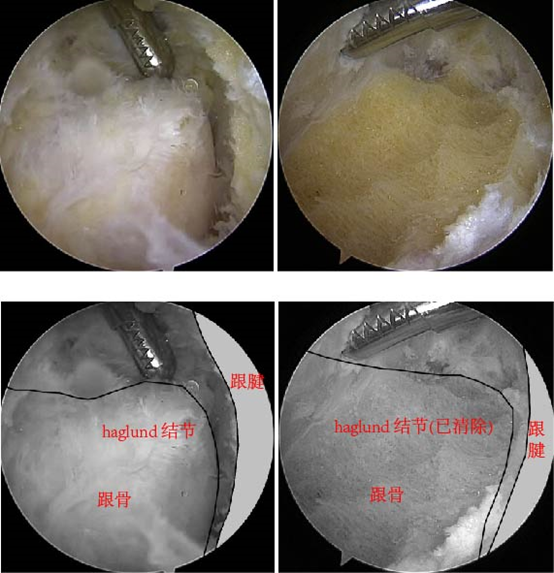

图15:关节镜下跟腱止点清理术,左图为Hugland结节切除前,右图为切除后